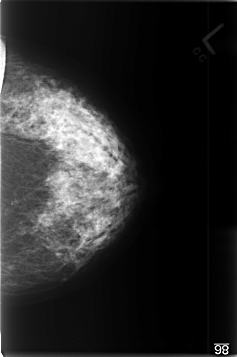

C_0350_1.LEFT_MLO

LEFT_MLO LINES 4536 PIXELS_PER_LINE 3024 BITS_PER_PIXEL 12 RESOLUTION 50 NON_OVERLAY